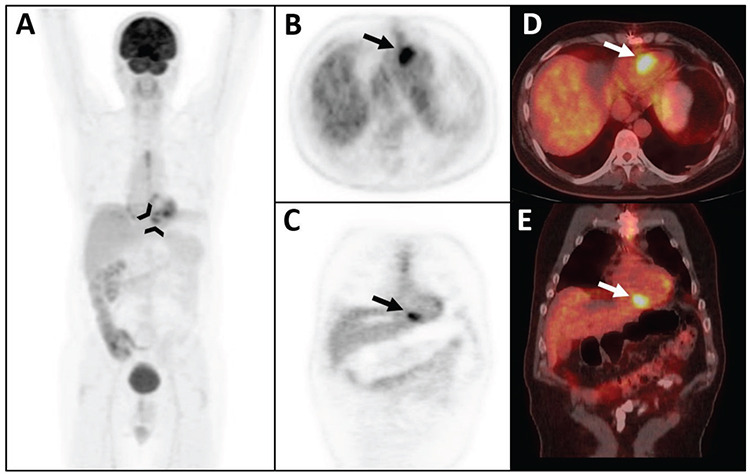

原始神经外胚层肿瘤(PNET)是小圆形细胞癌家族中罕见的侵袭性肿瘤。一般来说,PNET 主要分为两类:中枢神经系统 PNET 和周围神经系统 PNET。在此,我们报告了利用 18F- 氟脱氧葡萄糖(18F-FDG)正电子发射断层扫描/计算机断层扫描(PET/CT)成像对一例罕见的孤立性心脏 PNET 进行治疗反应评估的结果。鉴于通常可观察到生理性心脏 FDG 摄取,评估心肌中的 FDG 受体病变对 FDG PET/CT 来说是一项挑战。本病例的意义在于该疾病的罕见性和 FDG PET/CT 成像部位的挑战性。

Primitive neuroectodermal tumors (PNETs) are rare and aggressive members of the small round cell carcinoma family. Generally, PNETs are classified into two main groups: PNETs of the central nervous system and PNETs of the peripheral nervous system. Herein, we report the therapy response assessment of a rare case of isolated cardiac PNET using 18F-fluorodeoxyglucose (18F-FDG) positron emission tomography/computed tomography (PET/CT) imaging. Given that physiological cardiac FDG uptake is typically observed, assessing FDG avid lesions in the myocardium presents a challenge for FDG PET/CT. This case holds significance because of the rarity of the disease and the challenging nature of the site for FDG PET/CT imaging.